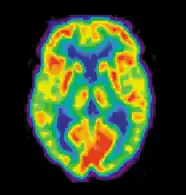

Позитронно-эмиссионная томография

Позитронно-эмиссионная томография (ПЭТ) измеряет выброс радиоактивно меченых метаболически активных химических веществ, введённых в кровеносное русло. Информация обрабатывается компьютером в 2- или 3-мерные изображения распределения этих химических веществ в головном мозге[7]. Испускающие позитроны радиоизотопы производит циклотрон и химические вещества маркируют радиоактивными атомами. Радиоактивно меченое образование, именуемое радиоактивный индикатор, вводят путём инъекции в кровеносное русло и в конечном счёте оно достигает головного мозга. Сенсоры в ПЭТ-сканере регистрируют радиоактивность, когда радиоактивный индикатор накапливается в разных структурах головного мозга. Компьютер использует информацию, собранную от сенсоров для создания 2- и 3-мерных разноцветных изображений, отражающих распределение индикатора в мозге. В настоящее врем нередко используются целые группы разнообразных лигандов для картирования различных аспектов активности нейромедиаторов. Тем не менее, наиболее часто используемым ПЭТ-индикатором остается меченая форма глюкозы (см. Фтордезоксиглюкоза (ФДГ)), показывающая распределение метаболической активности клеток головного мозга.

Самое большое преимущество ПЭТ в том, что разные радиоиндикаторы могут показывать кровообращение, оксигенацию и метаболизм глюкозы в тканях работающего мозга. Эти измерения отображают объём активности головного мозга в его разных участках и дают возможность больше изучить, как он работает. ПЭТ превосходит остальные методики, визуализирующие метаболизм в отношении разрешения и скорости (делает скан в течение 30 с). Улучшенная разрешающая способность дала возможность лучше изучить мозг, активированный определённым заданием. Главный недостаток ПЭТ заключается в том, что радиоактивность быстро распадается, это ограничивает мониторинг только коротких заданий[8]. До того, как стала доступной ФМРТ, ПЭТ была главным методом функциональной (в противоположность структурной) методикой нейровизуализации и до сих пор продолжает делать большой вклад в неврологию.

ПЭТ также используют для диагностики болезней головного мозга, в первую очередь потому что опухоли головного мозга, инсульты и повреждающие нейроны заболевания, вызывающие деменцию (такие как болезнь Альцгеймера) очень нарушают метаболизм мозга, что ведёт к легко заметным изменениям на ПЭТ-сканах. ПЭТ, вероятно, наиболее полезна в ранних случаях определённых деменций (классический пример — болезнь Альцгеймера и болезнь Пика), где ранние нарушения особо диффузные и ведут к слишком маленьким различиям в объёме мозга и его макроскопической структуре, чтобы быть заметными на КТ или стандартной МРТ, которые не имеют возможности отличить их от обычной возрастной инволюции (атрофии), не вызывающей клинической деменции.